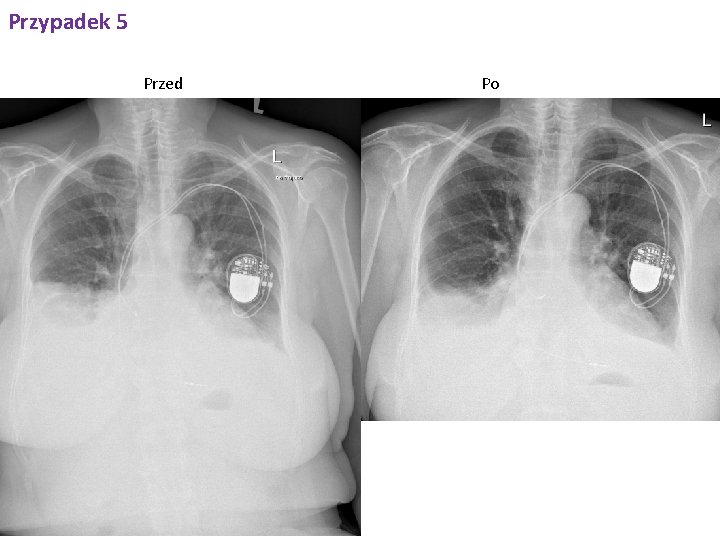

Przypadek 5 RTG klatki piersiowej PA i bok. 13. 11. 2017 Stan po nakłuciu prawej jamy opłucnej - cech odmy opłucnowej nie stw. się. W por. do bad. poprz. z dn. 09. 11. 2017 r - regresja ilości płynu w prawej jamie opłucnej - aktualnie sięga przedniego odc. żebra VI; po stronie lewej płyn spłycający kąt p-ż; obustronnie, nad poziomem płynu zmiany niedodmowe/niedodmowo-zapalne. Drobne zmiany guzkowo-włókniste w szczycie lewego płuca. Poza tym pola płucne bez zmian ogniskowych, o cechach niewydolności w krążeniu płucnym. Wnęki płucne poszerzeone, najpewniej naczyniowo. Ocena sylwetki serca utrudniona - wydaje się być powiększona. Aorta piersiowa w normie. Zmiany zwyr. kręgosłupa Th. Stan po implantacji kardiostymulatora 2 elektrodowego; końcówki elektrod rzutują się w PP i PK ; ciągłość elektrod zachowana;

Przypadek 5 Przed Po

Przypadek 5 W trakcie pobytu włączono leczenie moczopędne, wykonano diagnostyczne nakłucie jamy opłucnowej prawej w którym odbarczono ok. 100 ml jasnożółtego, przejrzystego płynu. W badaniu cytologicznym wykryto komórki atypowe, prawdopodobnie nowotworowe ("cellulae atypicae, probaliter carcinomatosae" - prof dr hab n. med. Marian Danielewicz).